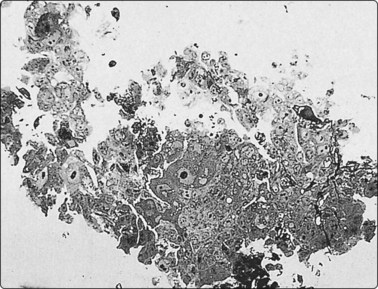

Tissue fragments and cell blocks

Sometimes, a thin core or fragments of tissue may be obtained with a standard 22-gauge needle (Fig. 2.14). Tissue fragments are fixed in 5–10% buffered isotonic formalin and processed as for routine histology.

image

Fig. 2.14 Tissue core by 22-gauge lumbar puncture needle

Tissue section of a 22-gauge lumbar puncture needle core from a well-differentiated hepatocellular carcinoma (H&E, LP).

Some laboratories recommend the routine preparation of cell blocks for paraffin embedding of FNB samples. Cell blocks may give a better idea of tissue architecture and allow multiple sections for panels of immune markers with controls.19-21 However, they are relatively time consuming and costly compared to routine smears.22 We use cell blocks selectively, mainly if a need for immunocytochemistry is anticipated. Cell blocks are helpful if samples are heavily admixed with blood. Surprisingly good tissue fragments are often found in a cell block even when smears show only blood.

More recently, we have developed a simplified technique for cell blocks that we call ‘cell buttons’, shown diagrammatically in Figure 2.15. It is applicable to cell-rich tissues such as lymph nodes and cellular neoplasms. A drop of thick, creamy material obtainable from such tissues using a 27–25-gauge needle without aspiration is gently expelled onto a glass slide as usual, but is not spread or smeared. After a few seconds to allow the drop to adhere to the slide, the slide is carefully immersed in 90% ethanol. The sample remains stuck to the slide as a drop (‘button’). Alcohol-fixation, unlike formalin, holds the sample together. After fixation, the ‘button’ is gently detached with a scalpel blade and processed like a small biopsy. The amount of tissue obtained in this way can be substantial, cell preservation and fixation is excellent, and the material is well suited to immunocytochemical studies (Fig. 2.16). An advantage over a conventional cell block is that the cell material is concentrated, whereas multiple sections may be necessary to find scanty tissue fragments in a cell block.

Fig. 2.15 Preparation of a ‘cell button’

(A) The FNB sample is blown onto a clean and dry microscopy slide; (B) The sample/drop is left untouched on the slide a few seconds to adhere without drying; (C) The slide with the sample is immersed in 95% ethanol and left to fix; (D) The solidified fixed ‘cell button’ is carefully removed from the slide with a scalpel and processed routinely like any small biopsy.

image image image

Fig. 2.16 FNB with ‘cell button’

FNB of peripheral lung tumor: (A) Air-dried direct smear (Diff-Quik, HP); (B, C) Tissue section of ‘cell button’; solid islands/cords of tumor tissue with a prominently vascular stroma (H&E, HP); positive synaptophysin (HP). Diagnosis of peripheral carcinoid tumor.